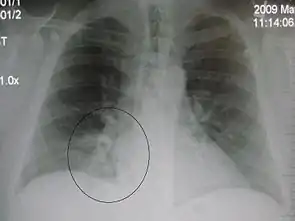

A chest X-ray showing a very prominent wedge-shape bacterial pneumonia in the right lung

The discovery of x-rays made it possible to determine the anatomic type of pneumonia without direct examination of the lungs at autopsy and led to the development of a radiological classification. Early investigators distinguished between typical lobar pneumonia and atypical (e.g. Chlamydophila) or viral pneumonia using the location, distribution, and appearance of the opacities they saw on chest x-rays. Certain x-ray findings can be used to help predict the course of illness, although it is not possible to clearly determine the microbiologic cause of a pneumonia with x-rays alone.